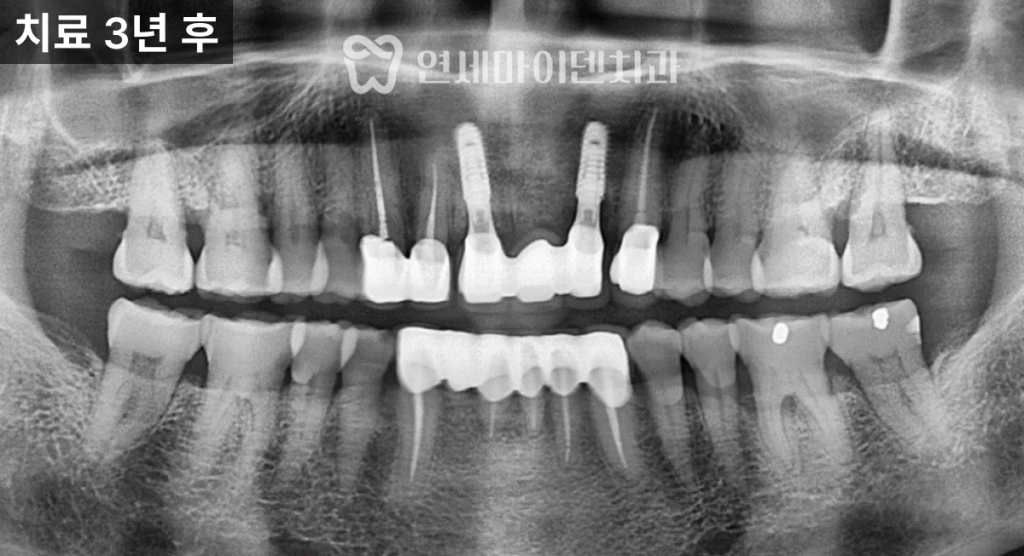

정밀 촬영 결과

두 개의 앞니 뿌리 끝, 즉 치근단 부위에서

뚜렷한 염증 소견이 확인되었습니다.한쪽 치아는

뼈 손상이 심해 예후가 불량한 상태였고,

다른 한쪽은

염증이 국소적으로 제한되어 있어

신경치료 후 경과를 지켜볼 수 있는 상황이었습니다.이에 따라 치료 계획은 다음과 같이 세웠습니다.

임플란트로 치료한 앞니는

안정적으로 자리 잡았고,신경치료를 시행한 치아는

치근단 낭성 병변이

자연스럽게 치유되면서

추가적인 치근단 수술 없이

회복을 확인할 수 있었습니다.

최종 보철을 통해

기능과 심미성을 모두 회복했으며,해당 케이스는

치료 후 3년이 지난 현재까지도

안정적으로 유지되고 있습니다.